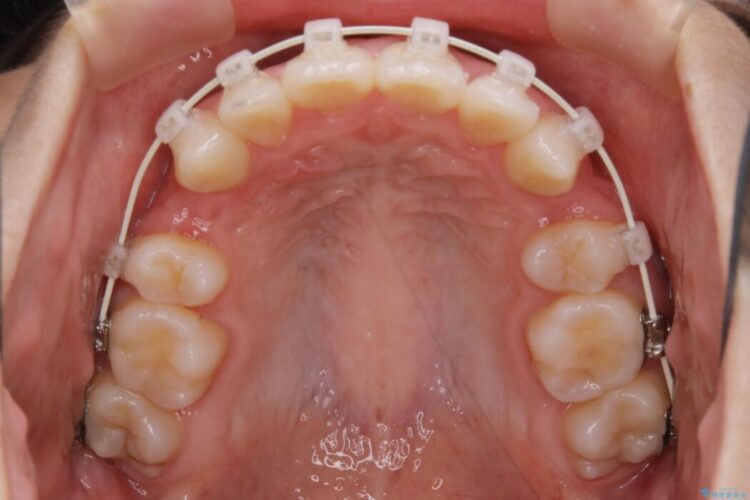

- 矯正装置:ワイヤー(審美装置)

検査したところ歯に対して骨が上顎・下顎共に小さいことがわかりました。

それによりスペースが少なく歯列がガタついたり前方傾斜する生え方となっていました。

よって本症例では抜歯により歯の本数を減らすことにより整えるスペースを確保してワイヤー装置にて歯列矯正を行うこととしました。

本症例の患者様は顎の骨が小さく歯をきれいに並べるための隙間がないため、歯が重なったり傾斜してしまっていました。

抜歯を行うことによりスペースを確保し、小さい骨幅でも歯並びを整えることができます。